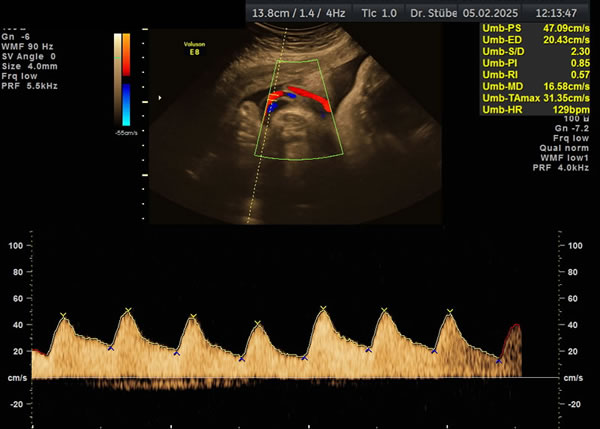

Wachstums- und Dopplersonographie

Die Dopplersonographie beinhaltet die Untersuchung der mütterlichen und kindlichen Gefäße. Sie liefert Informationen über die Versorgung des Kindes durch die Plazenta und den aktuellen Zustand des Kindes.

Sollten auffällige Befunde vorliegen, können durch engmaschige Kontrollen Wachstumsverzögerungen frühzeitig erkannt werden.

Dopplersonographie